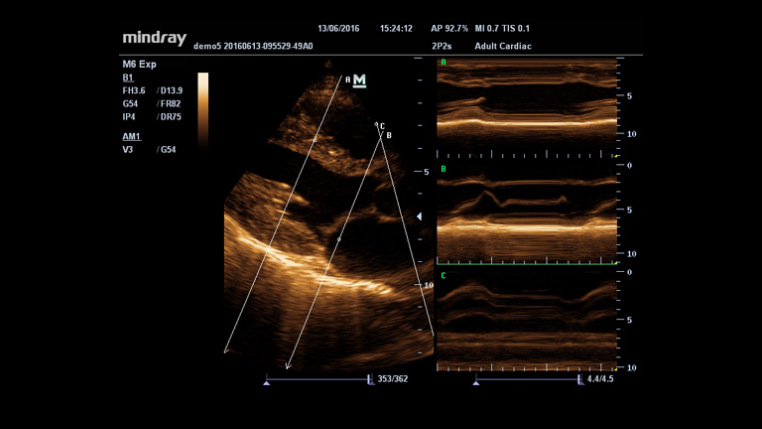

System diagnostyki USG

Specjaliści kliniczni przebyli długą i trudną drogę, aby uzyskać możliwość stosowania diagnostyki obrazowej o wysokim standardzie przy łóżku pacjenta poddawanego intensywnej opiece medycznej. Dotychczas wybór wielkości i wydajności aparatów USG był ograniczony. Mając na względzie dostępność opieki zdrowotnej, Firma Mindray wprowadziła nowy aparat M6, idealnie łączący w sobie możliwości i rozmiar potrzebne do niezawodnego diagnozowania pacjenta przy łóżku.